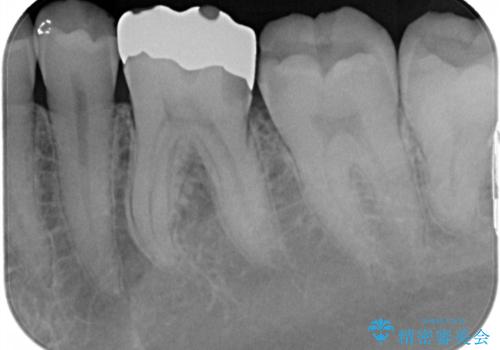

1番奥の歯のセラミック治療をご希望されましたが、レントゲンなどの診査の結果、大きな虫歯などもありませんでした。

それよりも奥から2番目の歯のほうが、適合不良の銀のつめものが入っており、大きな虫歯が疑われました。

虫歯の大きさや形を加味して、1番奥を保険治療、奥から2番目をセラミック治療で行うことになりました。